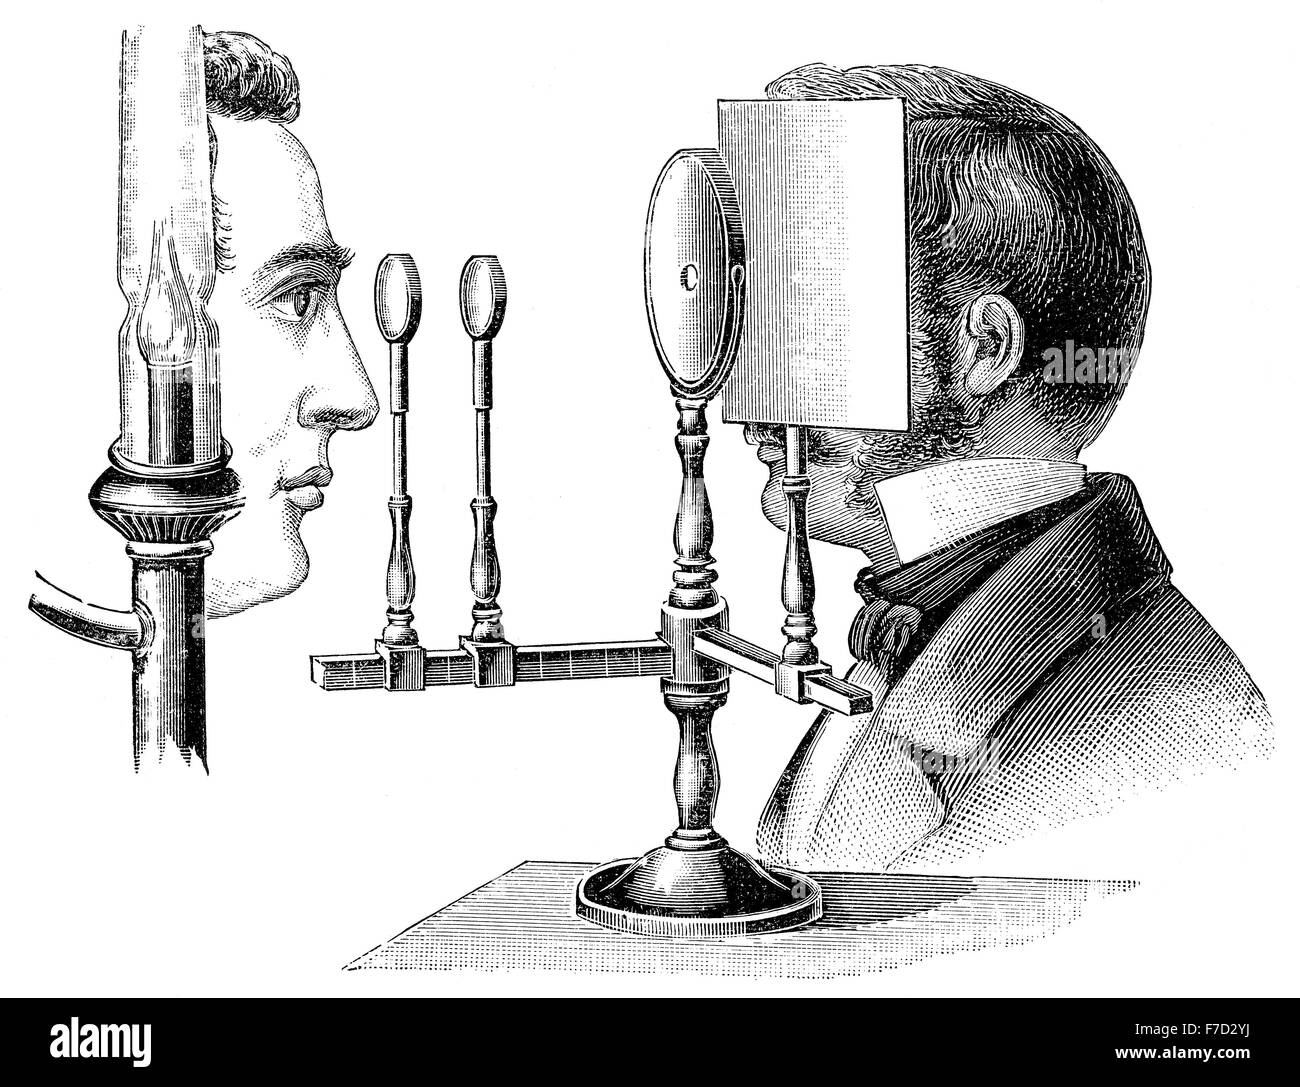

Ophthalmoscope, funduscope to see inside the fundus of the eye, Hermann Ludwig Ferdinand von Helmholtz, 1821-1894, German physic Stock Photohttps://www.alamy.com/image-license-details/?v=1https://www.alamy.com/stock-photo-ophthalmoscope-funduscope-to-see-inside-the-fundus-of-the-eye-hermann-90642150.html

Ophthalmoscope, funduscope to see inside the fundus of the eye, Hermann Ludwig Ferdinand von Helmholtz, 1821-1894, German physic Stock Photohttps://www.alamy.com/image-license-details/?v=1https://www.alamy.com/stock-photo-ophthalmoscope-funduscope-to-see-inside-the-fundus-of-the-eye-hermann-90642150.htmlRMF7D2YJ–Ophthalmoscope, funduscope to see inside the fundus of the eye, Hermann Ludwig Ferdinand von Helmholtz, 1821-1894, German physic